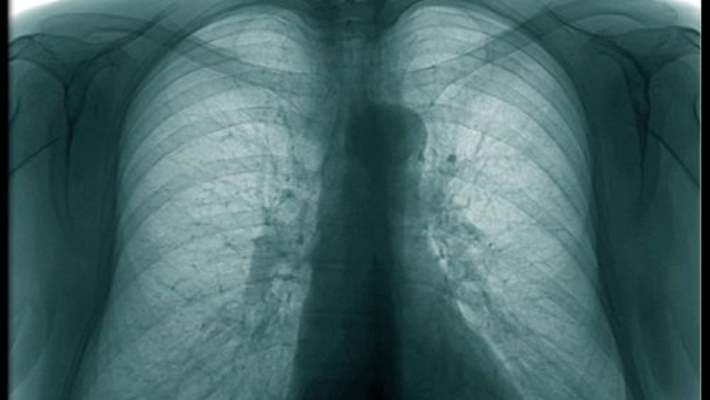

Göğüs röntgeni kalbinizin, akciğerlerinizin, kan damarlarınızın, kaburgalarınızın ve omurganızdaki kemiklerin görüntülerini gösterir. Eğer göğüs ağrısı ve nefes kesilmesi şikayetleriyle doktora ya da acil servise giderseniz çektireceğiniz bir göğüs röntgeni kalp yetmezliği, akciğer çökmesi, zatürree (pnömoni) ya da kaburga kırığı olup olmadığının saptanmasına yardımcı olabilir.

Göğüs röntgeni ayrıca akciğerinizde toplanan sıvıyı ya da akciğer çevresinde meydana gelen boşlukları, kalp genişlemesi, amfizem, kanser ya da diğer sağlık sorunlarını da saptayabilir. Bazı kişilerin, sağlık sorunlarında iyileşme ya da kötüleşme olup olmadığını taramak için belli bir süre boyunca kişinin bir dizi göğüs röntgeni çektirmesi gerekebilir.

Göğüs röntgeni, radyografik muayenenin en yaygın olarak uygulandığı alandır. Doktorunuz, bir kalp ya da akciğer hastalığınız olduğundan şüpheleniyorsa genellikle, size ilk uygulanacak işlemlerin arasında göğüs röntgeni de olacaktır.

Göğüs röntgeni aşağıdakileri gösterebilir:

- Akciğerlerinizin durumu. Göğüs röntgenleri, akciğer kanserini ve akciğer enfeksiyonunu tespit edebilir. Ayrıca amfizem ya da kistik fibrozis gibi bazı kronik akciğer hastalıklarını da gösterebilir.

- Kalple ilişkili akciğer hastalıkları. Göğüs röntgenleri, akciğerinizdeki kalp sorunlarından kaynaklanan değişiklikleri ya da anormallikleri ortaya çıkarabilir. Örneğin, konjestif kalp yetmezliği sonucunda akciğerlerinizde sıvı toplanabilir (pulmoner ödem ya da akciğer ödemi).

- Kalbinizin büyüklüğü ve şekli. Kalbinizin büyüklüğünde ve şeklinde gerçekleşen değişiklikler; kalp yetmezliği, konjenital (doğuştan) kalp hastalıkları, kalp çevresinde sıvı birikimi (perikardiyal efüzyon) ya da kalp kapakçığında meydana gelen bir veya daha fazla sorun gibi çeşitli sağlık durumlarına işaret edebilir.

- Kan damarları. Kalbinizin yakınındaki geniş kan damarlarının –aort ve pulmoner arterler ve damarlar– ana hatları röntgende göründüğü için, aort anevrizmalarını ya da diğer damar problemlerini ortaya çıkarabilir.

- Kalsiyum tortuları. Göğüs röntgeni, kalbinizde ve kan damarlarınızda bulunan kalsiyumu saptayabilir. Kalsiyumun varlığıysa kalp kapakçıklarında, koroner arterlerde, kalp kaslarında ya da kalbi çevreleyen koruyucu kesede hasara işaret edebilir. Akciğerlerinizde kalsiyum tortusu olması, eski ve iyileşmiş enfeksiyondan ya da daha ciddi bir hastalıktan kaynaklanabilir.

X-ışınları, vücut yapılarından ve dokulardan farklı hızlarda geçerler. Kemik oldukça yoğun bir yapıdır ve radyasyonun çoğunun geçişini engeller, bu nedenle filmdeki kemik görüntüleri beyaz görünür. Kalbiniz de radyasyonun bir kısmının geçişini engellediği için, filmde açık renkli bir alan olarak görünür. Akciğerler hava ile doludur, bu nedenle radyasyonun çok azının geçişini engellerler ve koyu renkli görüntüler oluştururlar.

Bir radyolog –röntgen ve diğer görüntüleme muayenelerini yorumlama üzerine uzmanlaşmış bir doktor– herhangi bir kalp problemi, kalp çevresinde sıvı birikimi, kanser, zatürree ve diğer akciğer hastalıkları ya da diğer sağlık sorunlarına dair işaretler arayarak görüntüleri analiz eder.